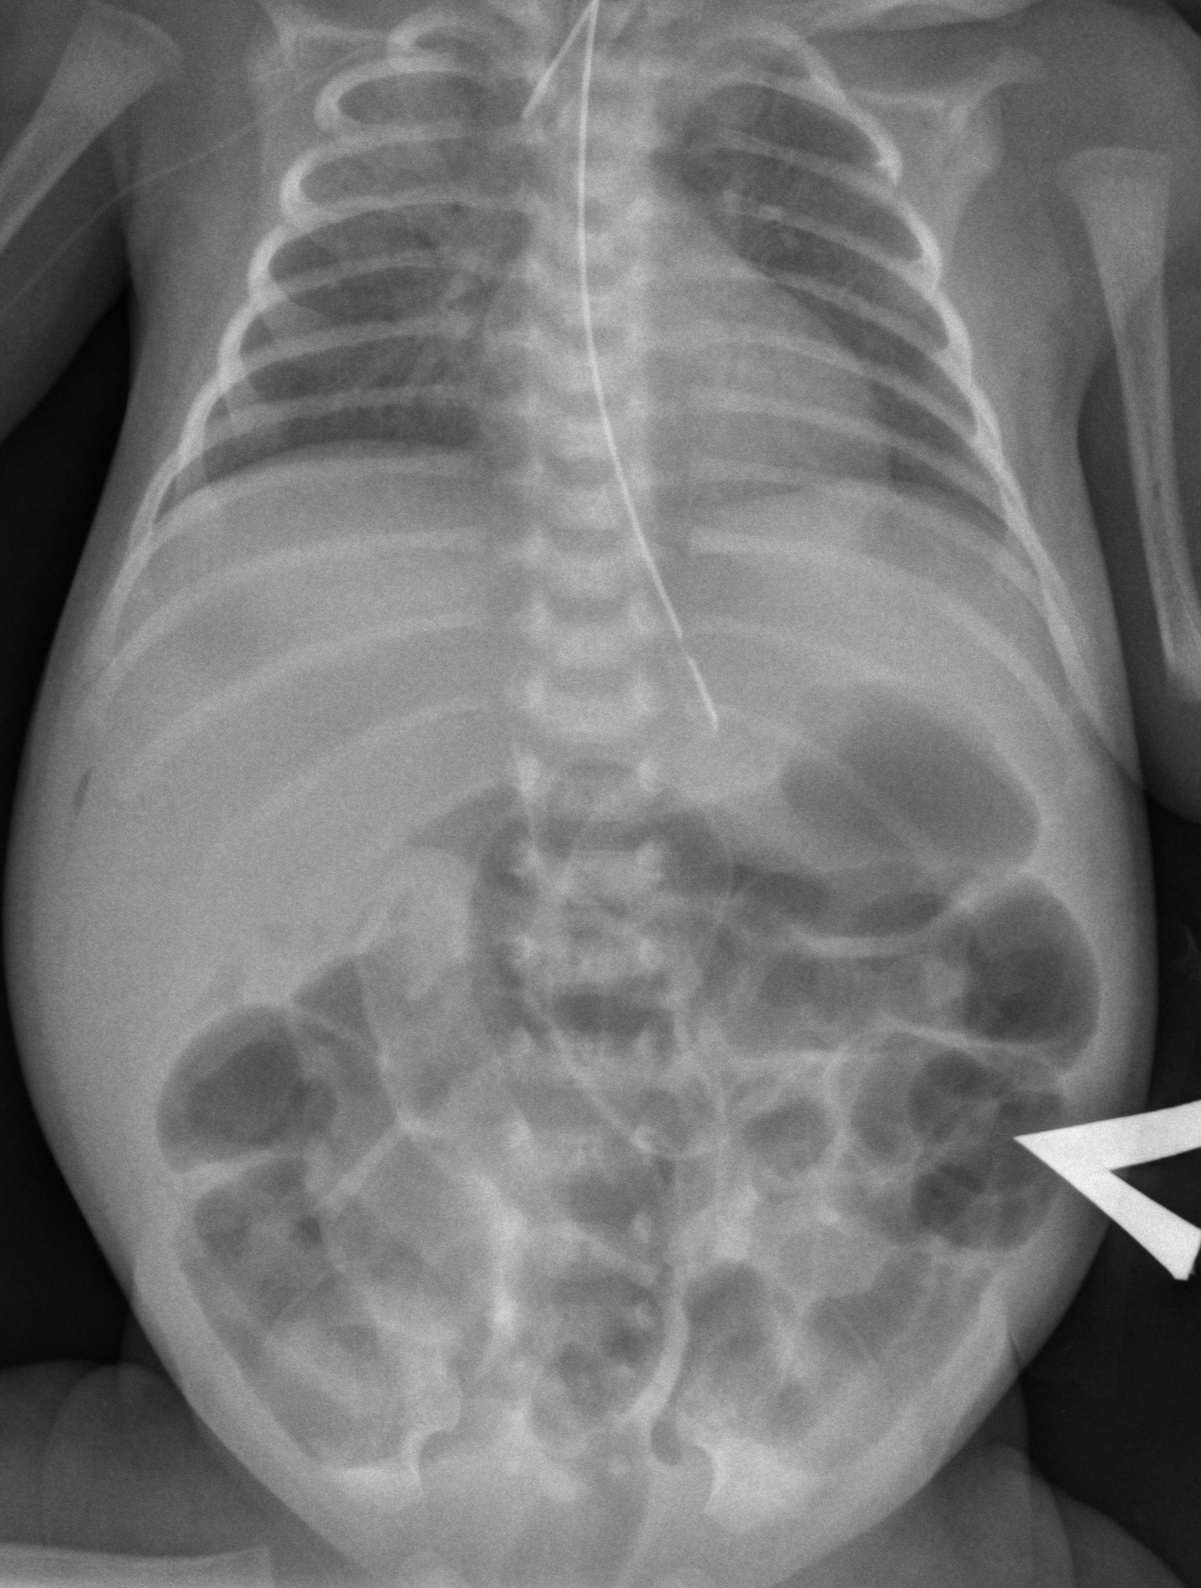

Современные технологии в медицине: рентгенодиагностика заболеваний желудка